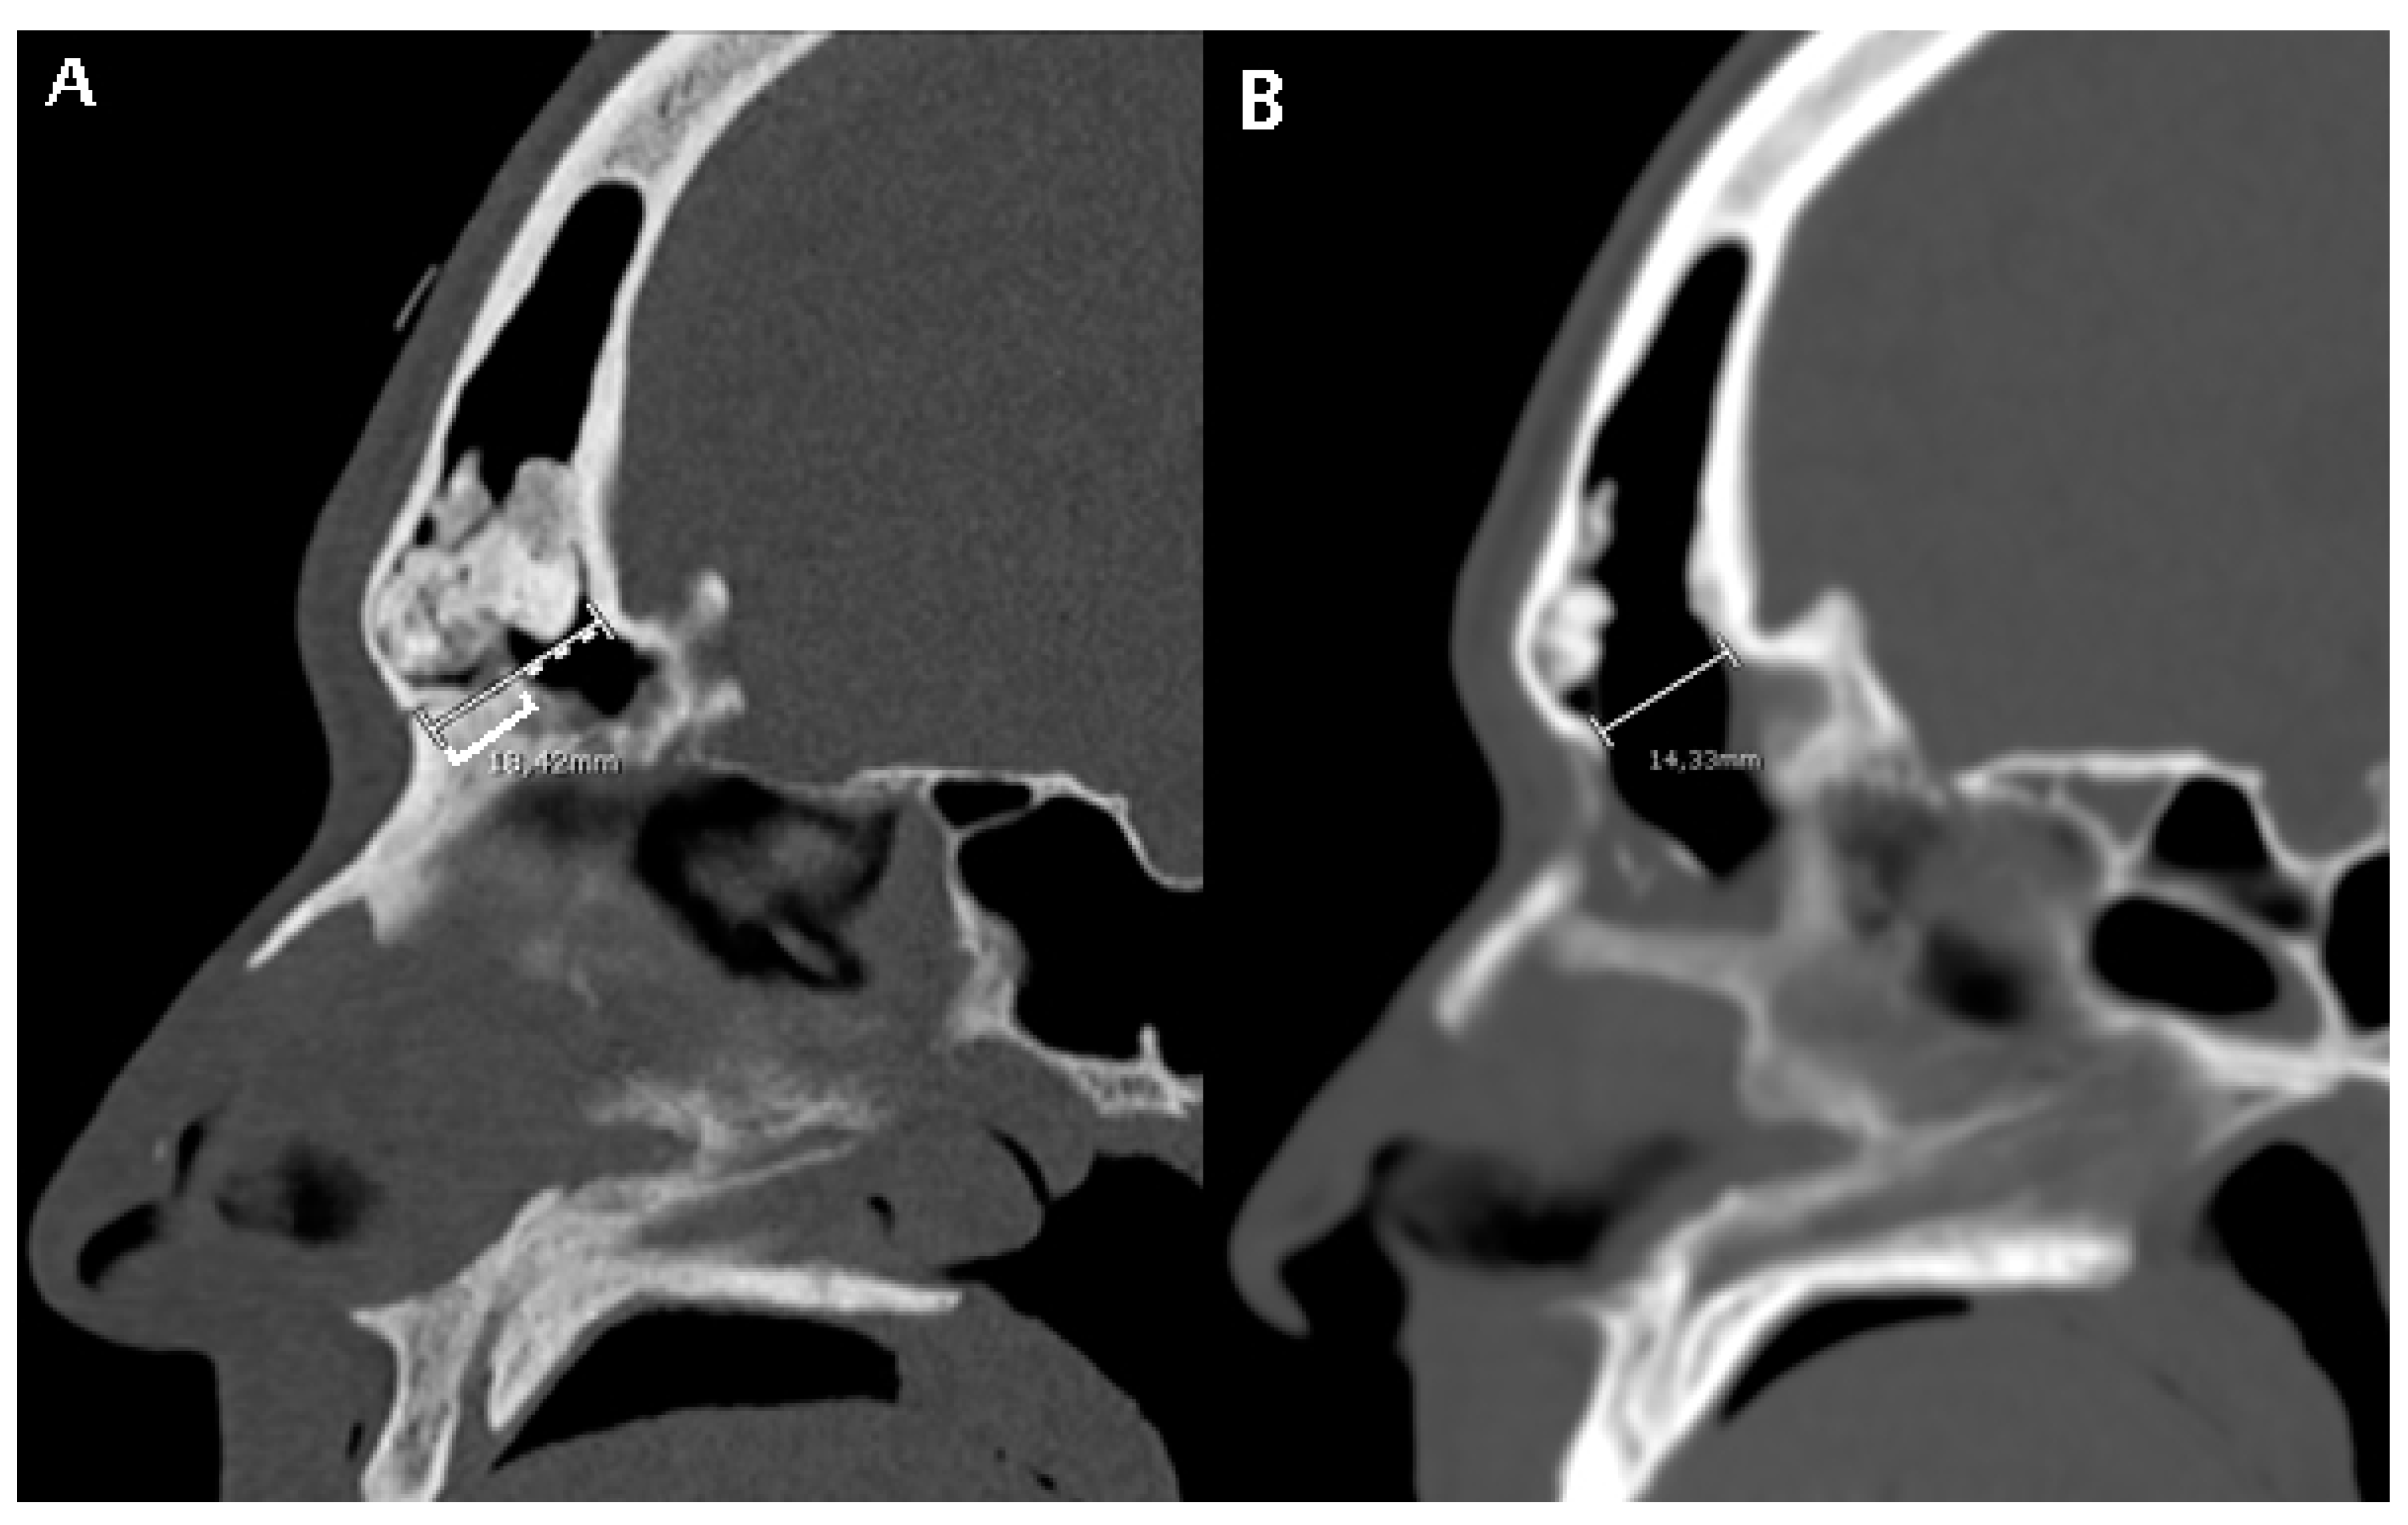

Figure 2. A patient subjected to a DRAF III for relapse of osteoma and fronto-orbital mucocele. (A) shows a pre-operative CT scan where FOAP max (white line) is measured as the sum of the mid-sagittal thickness of the nasal beak (white square bracket) and the mid-sagittal distance between the nasal beak and the most anterior skull base (white dotted line). (B) shows the post-operative CT scan on the same mid-sagittal section. The white line represents the maximum anteroposterior diameter of the frontal sinus neostium after surgery, which we termed obtained diameter (OD, see Figure 5).

High-resolution CT images were analyzed from all the patients included by two authors (C.C. and M.B.). Mid-sagittal images, identified by the location of the nasal septum and crista galli, were chosen for analysis and measurement. The minimum and maximum frontal sinus outflow anteroposterior diameters (FOAP min and FOAP max, respectively) were measured. The FOAP max was measured as the sum of 1) the mid-sagittal anteroposterior thickness of the nasal beak and 2) the mid-sagittal anteroposterior distance between the nasal beak and the anterior most skull base (Figure 2), as described in the study by Zhang et al. It corresponds to the distance between the nasion and the posterior wall of the frontal sinus.

The FOAP min was measured as the distance between the posterior edge of the frontal beak and the posterior wall of the frontal sinus, following the indications of the previously mentioned article (Figure 3).

In the subset of patients with available early post-operative CT scan, a post-operative radiological parameter was measured, that is the obtained diameter (OD). It was calculated on the same mid-sagittal section of the pre-operative CT scan, as the distance between the most anterior portion of the frontal neo-ostium and the most anterior portion of the anterior skull base, as shown in Figure 5. A correlation analysis between the FOAP min, FOAP max, and G-N angle with OD was performed by means of the Pearson correlation coefficient for continuous variables.